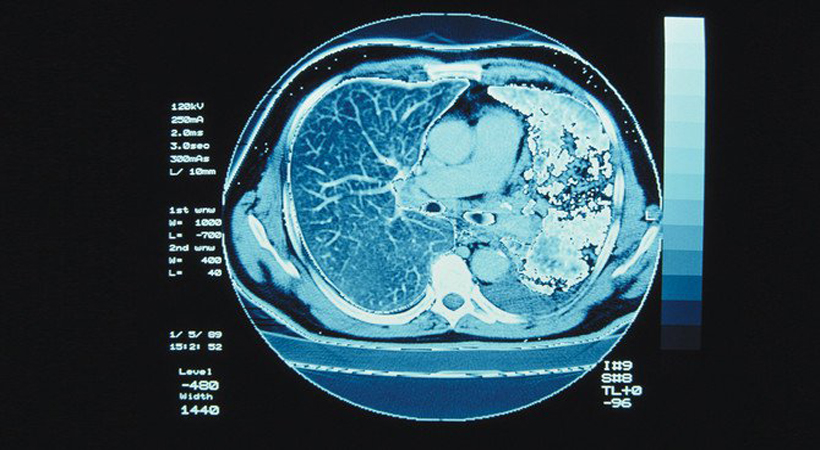

ജിദ്ദ: വര്ദ്ധിച്ചുവരുന്ന അര്ബുദരോഗ പ്രിരോധത്തിനായി ശക്തമായ നടപടികളുമായി സൗദി അറേബൃ. രോഗികളെ ചികിത്സിക്കാനുള്ള കൂടുതല് സൗകരൃങ്ങള് ഏര്പ്പെടുത്തുന്നതോടൊപ്പം രോഗ പ്രതിരോധത്തിനുള്ള നടപടികളും സ്വീകരിക്കാനുള്ള ഒരുക്കത്തിലാണ് ബന്ധപ്പെട്ട അധികൃതര്.

ഈ അടുത്തകാലത്ത് പുറത്തുവിട്ട കണക്കുപ്രകാരം സൗദിയിലെ 14.9 ശതമാനം പുരുഷന്മാരിലും 30.1 സ്ത്രീകളിലും അര്ബുദരോഗം കണ്ടെത്തിയതായാണ് റിപ്പോര്ട്ട് ചെയ്തിട്ടുള്ളത്. അതുകൊണ്ട്തന്നെ രോഗപ്രതിരാധത്തിന് വന് പ്രാധാനൃമാണ് അധികൃതര് നല്കിവരുന്നത്. സ്തനാര്ബുദം പ്രതിവര്ഷം 500 എന്ന തോതിലാണ് റിപ്പോര്ട്ട് ചെയ്തിട്ടുള്ളത്.

അര്ബുദ രോഗം മൂലം നിരവധിപേരുടെ ജീവനാണ് സൗദിയില് ഹനിക്കപ്പെടുന്നത്. അര്ബുദരോഗ പ്രതിരോധത്തിന് സൗദി അറേബൃ വിവിധ പദ്ധതികള് ആവിഷ്ക്കരിച്ചിട്ടുണ്ട്. രോഗത്തിനെതിരെ പൊതുജനങ്ങളെ ബോധവത്കരിക്കും. സൗദിയിലൊട്ടുക്കും കൃാന്സര് സെന്റെുകള് സജീവമാക്കും. പാലിയേറ്റീവ് കേന്ദ്രങ്ങളുടെ എണ്ണം വര്ദ്ദിപ്പിക്കും. പുകവലി മൂലമുണ്ടാകുന്ന കൃാന്സര് രോഗങ്ങളെ കുറിച്ച് ബോധവത്കരിക്കും. കൃാന്സര് പ്രതിരോധത്തില് ഏറ്റവും മുന്പന്തിയിലെത്താനുള്ള ശ്രമമാണ് സൗദി അറേബൃ നടത്തുന്നത്.

അര്ബുദ രോഗത്തെ കുറിച്ച് അവബോധവും പ്രതിരോധ നടനടികളും സ്വീകരിച്ചില്ലെങ്കില് സൗദിയിലെ കൃാന്സര് രോഗികളുടെ എണ്ണം പതിന്മടങ്ങ് വര്ദ്ദിക്കുമെന്നാണ് ഇതുസംബന്ധമായ പഠനം വൃക്തമാക്കുന്നത്. സൗദിയില് 2008 – 2017 വര്ഷത്തില് 49 മുതല് 62 ശതമാനം വരെയാണ് കൃാന്സര് രോഗികള് വര്ദ്ദിച്ചിട്ടുണ്ട്. അതുകൊണ്ട്തന്നെ അര്ബുദ രോഗത്തിനെതിരെ ശക്തമായ നടപടികളാണ് സൗദി അറേബൃ സ്വീകരിക്കുക. പൊതുജനാരോഗൃം മുഖൃ അജണ്ഡയായി സ്വീകരിക്കാനുള്ള തയ്യാറെടുപ്പിലാണ് അധികൃതര്.